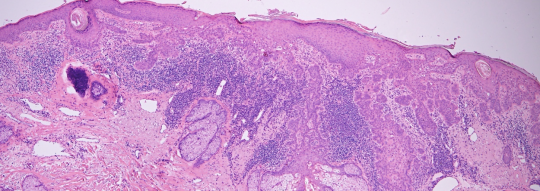

VA15: Right Dorsal Hand, Squamous Cell Carcinoma, Invasive, Keratoacanthoma type

- Arrows indicate extent of squamous mass